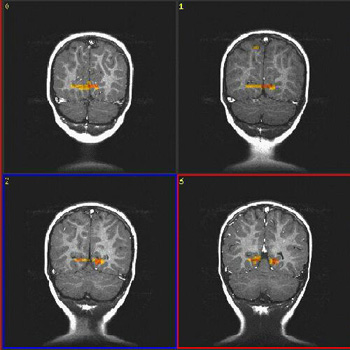

| Caso 3 |

| Paciente |

Niño de 4 años de edad con autismo

| Paradigma |

ACTIVADO: Presentación de luces intermitentes a 8 Hz, con gafas especiales colocadas

DESACTIVADO: Nada. Paciente sedado con nembutal |

| Estadísticas |

| Método estadístico |

Valor P |

Puntuación Z |

| Prueba T |

0,000002 |

4,0 |

| Activación |

Cortes coronales. Las áreas coloreadas en la figura se obtuvieron restando ACTIVADO a DESACTIVADO. Por consiguiente, el resultado muestra "desactivación", lo que representa la hiperextracción de oxígeno en las áreas visuales primarias (V1). Este hallazgo aparece constantemente en niños pequeños, ya sea despiertos o bajo sedación. |